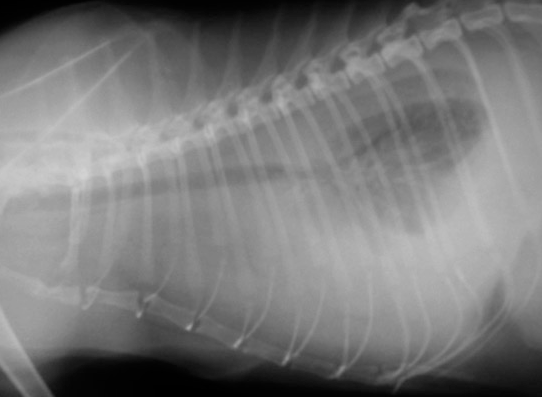

고양이 흉수 참고 자료

고양이 흉수에 대한 전반적인 분석 논문이다.

고양이의 흉수